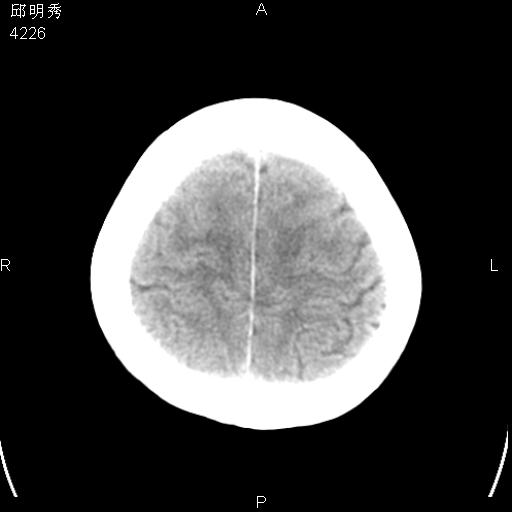

40f头晕十多天,右上肢麻木一天

脑白质变性或ms

脑白质脱髓鞘改变。

脑白质病;建议行mri检查。